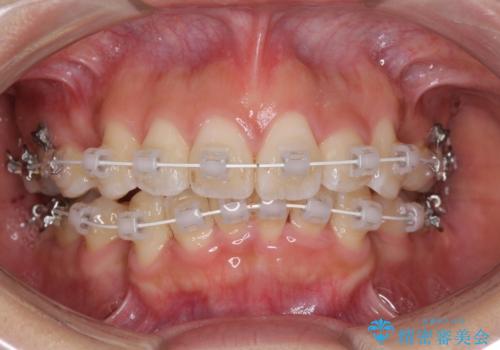

- 審美装置

- 2年5ヶ月

- 10-30回